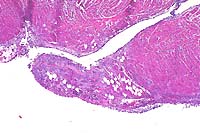

10x

obj

- Case 11-1. Spinal cord. A densely cellular neoplasm

effaces normal neuropil.